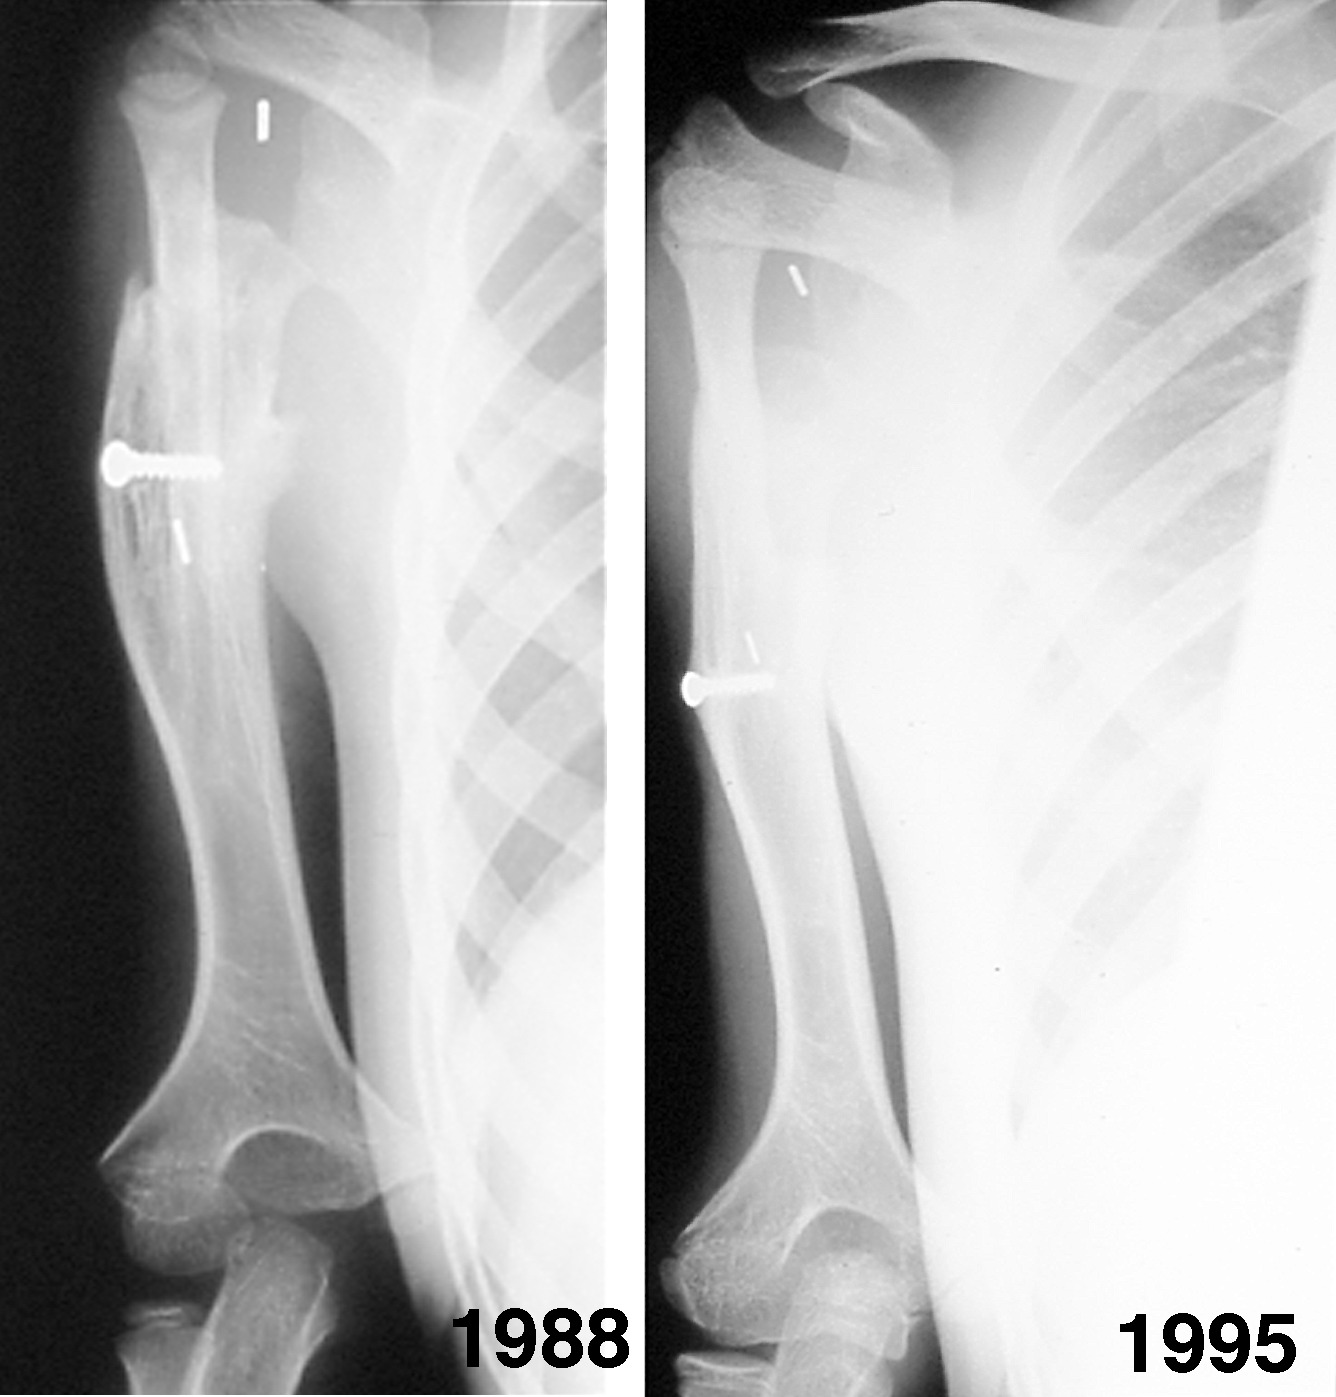

During this four-year period a further operation was required in September 1985 to stabilise the hand on the head of the fibula, for such was the growth rate that the hand was being progressively displaced in an ulnar direction, and the forearms became of similar length (Figure 17). The most recent X-rays reveal that the fibula growth plate had fused at age 15. This is the normal time for fusion of the proximal growth plate of the fibula. When the X-ray was compared with the opposite normal leg it was found that the transplanted epiphysis had grown at the same rate; it had averaged 0.5 cm per year (Figure 18). Functionally the patient has a very useful hand (Figure 19). The donor leg is stable at the knee, it is of normal length and there is no valgus deformity at the ankle joint.

The bone transplant united to the humerus and fibula growth occurred at a rate similar to the epiphyseal transfer in the previous patient (see Figure 18). He was lost to follow up for many years and was seen again at age 15, when it was found that the upper end of the fibula had dislocated anteriorly and superiorly (Figure 21 and Figure 22). Despite this deformity that understated the true growth in the transplant, he had pain-free movement of the shoulder and was a very active surfboarder.